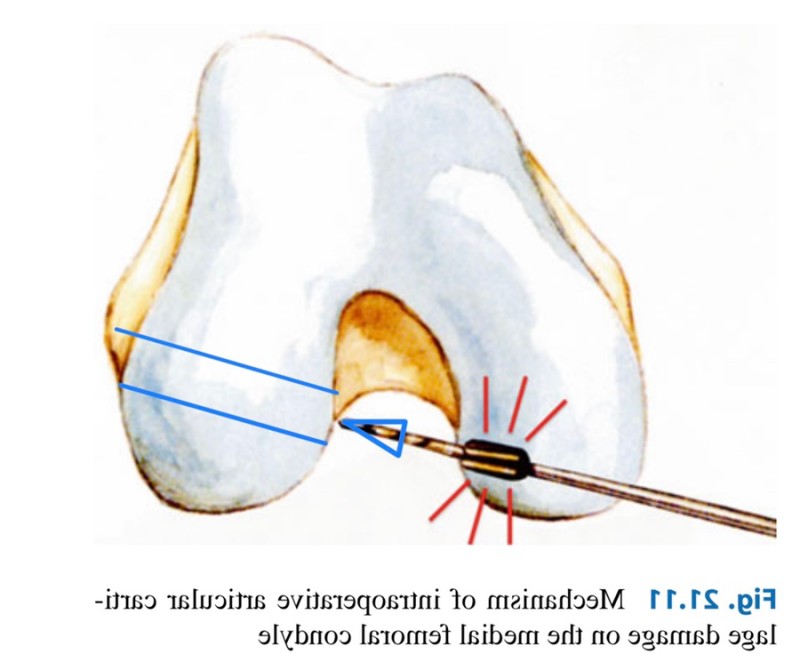

- Outside-in 술기

전내측 삽입구 술기의 장점을(해부학적 터널 시작점)

살리면서도, 단점(터널이 짧아짐)을 해결하기 위해

특수하게 제작된 가이드를 사용하여,

바깥에서 안으로 터널을 만드는 방법이 고안되어

최근에는 가장 해부학적이고 안정적인 터널 길이를

확보할 수 있는 outside-in 술기가 많이 사용됩니다.